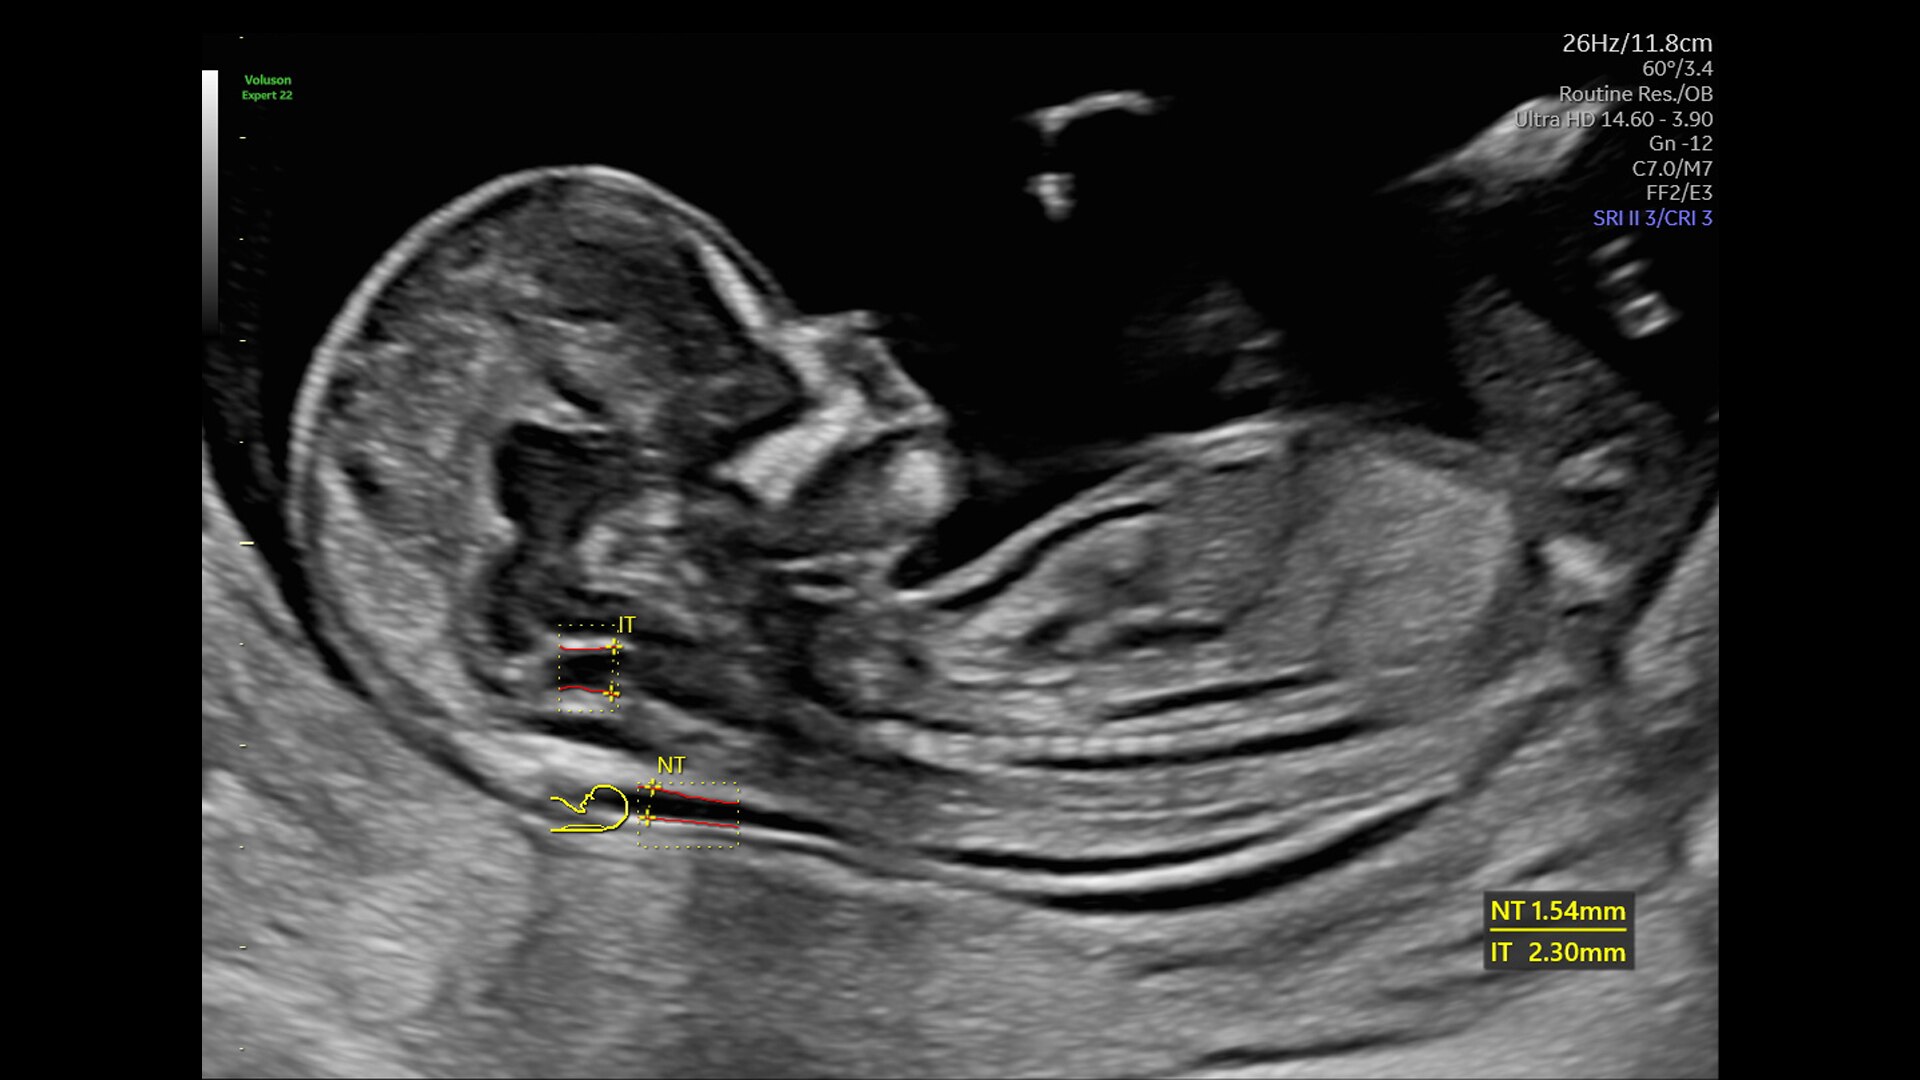

First Trimester Exams

Perform detailed exams with high-resolution for early insights to fetal health